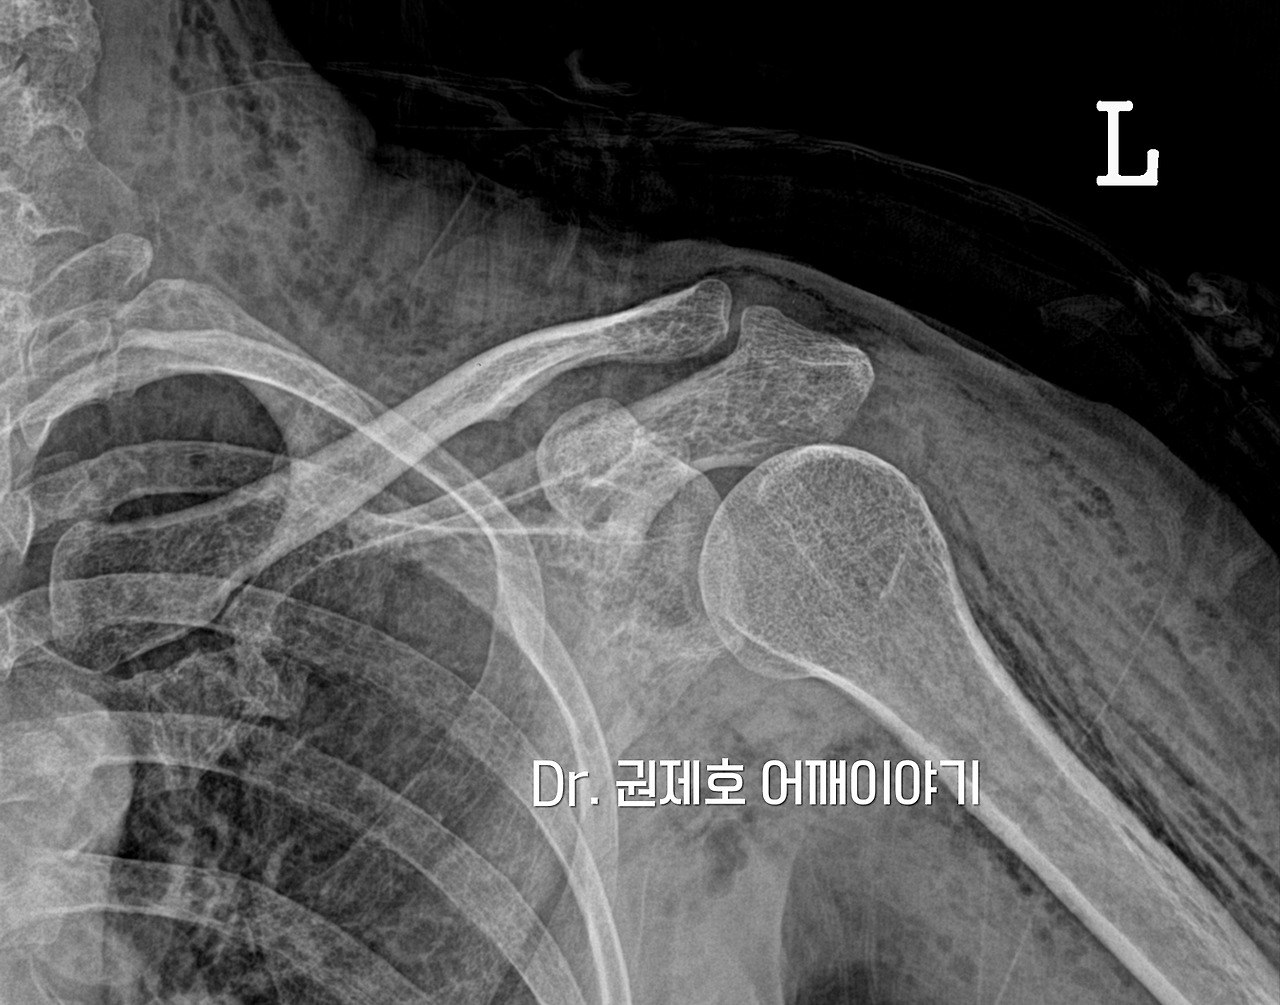

수술 후

수술을 마치고 나면 당연히 X-ray를 다시 촬영한다. 그래서 석회가 제거 되었는지 꼭 확인을 해야 한다.

동그랗게 있던 석회는 더이상 보이지 않는다.